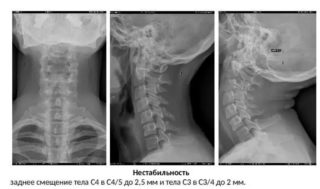

Снимки шейного отдела, выполненные в условиях проведения функциональных тестов:

- диагностируют смешение вышележащих позвонков относительно нижележащих;

- устанавливают характер и степень изменения передней стенки позвоночного канала.

При выполнении функционального теста врачи получают результаты:

- видят смещение позвонков друг относительно друга;

- могут установить степень изменения стенки позвоночного канала спереди и установить характер этих отклонений.